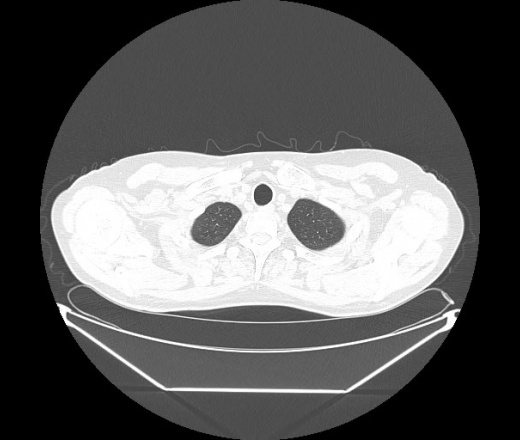

М. 1984 г.р.  Лихорадка 39, кашель , одышка.. и надоевший всем вопрос- "типично ли для ковид?" ( в настоящее время на него обязательно нужно дать ответ в своем протоколе)

На мой взгляд нетипично для ковид: много центрально-расположенных поражений, лобарное поражение нижней доли слева. 50/50

Не типичая картина для ковид.

КТ-признаки двусторонней бактериальной пневмонии.

Все верно, здесь абсолютно нетипичная картина, несмотря на матовое стекло с ретикулярными изменениями, но почему-то  посчитали иначе. Кстати,  "малыша" не заметили)?